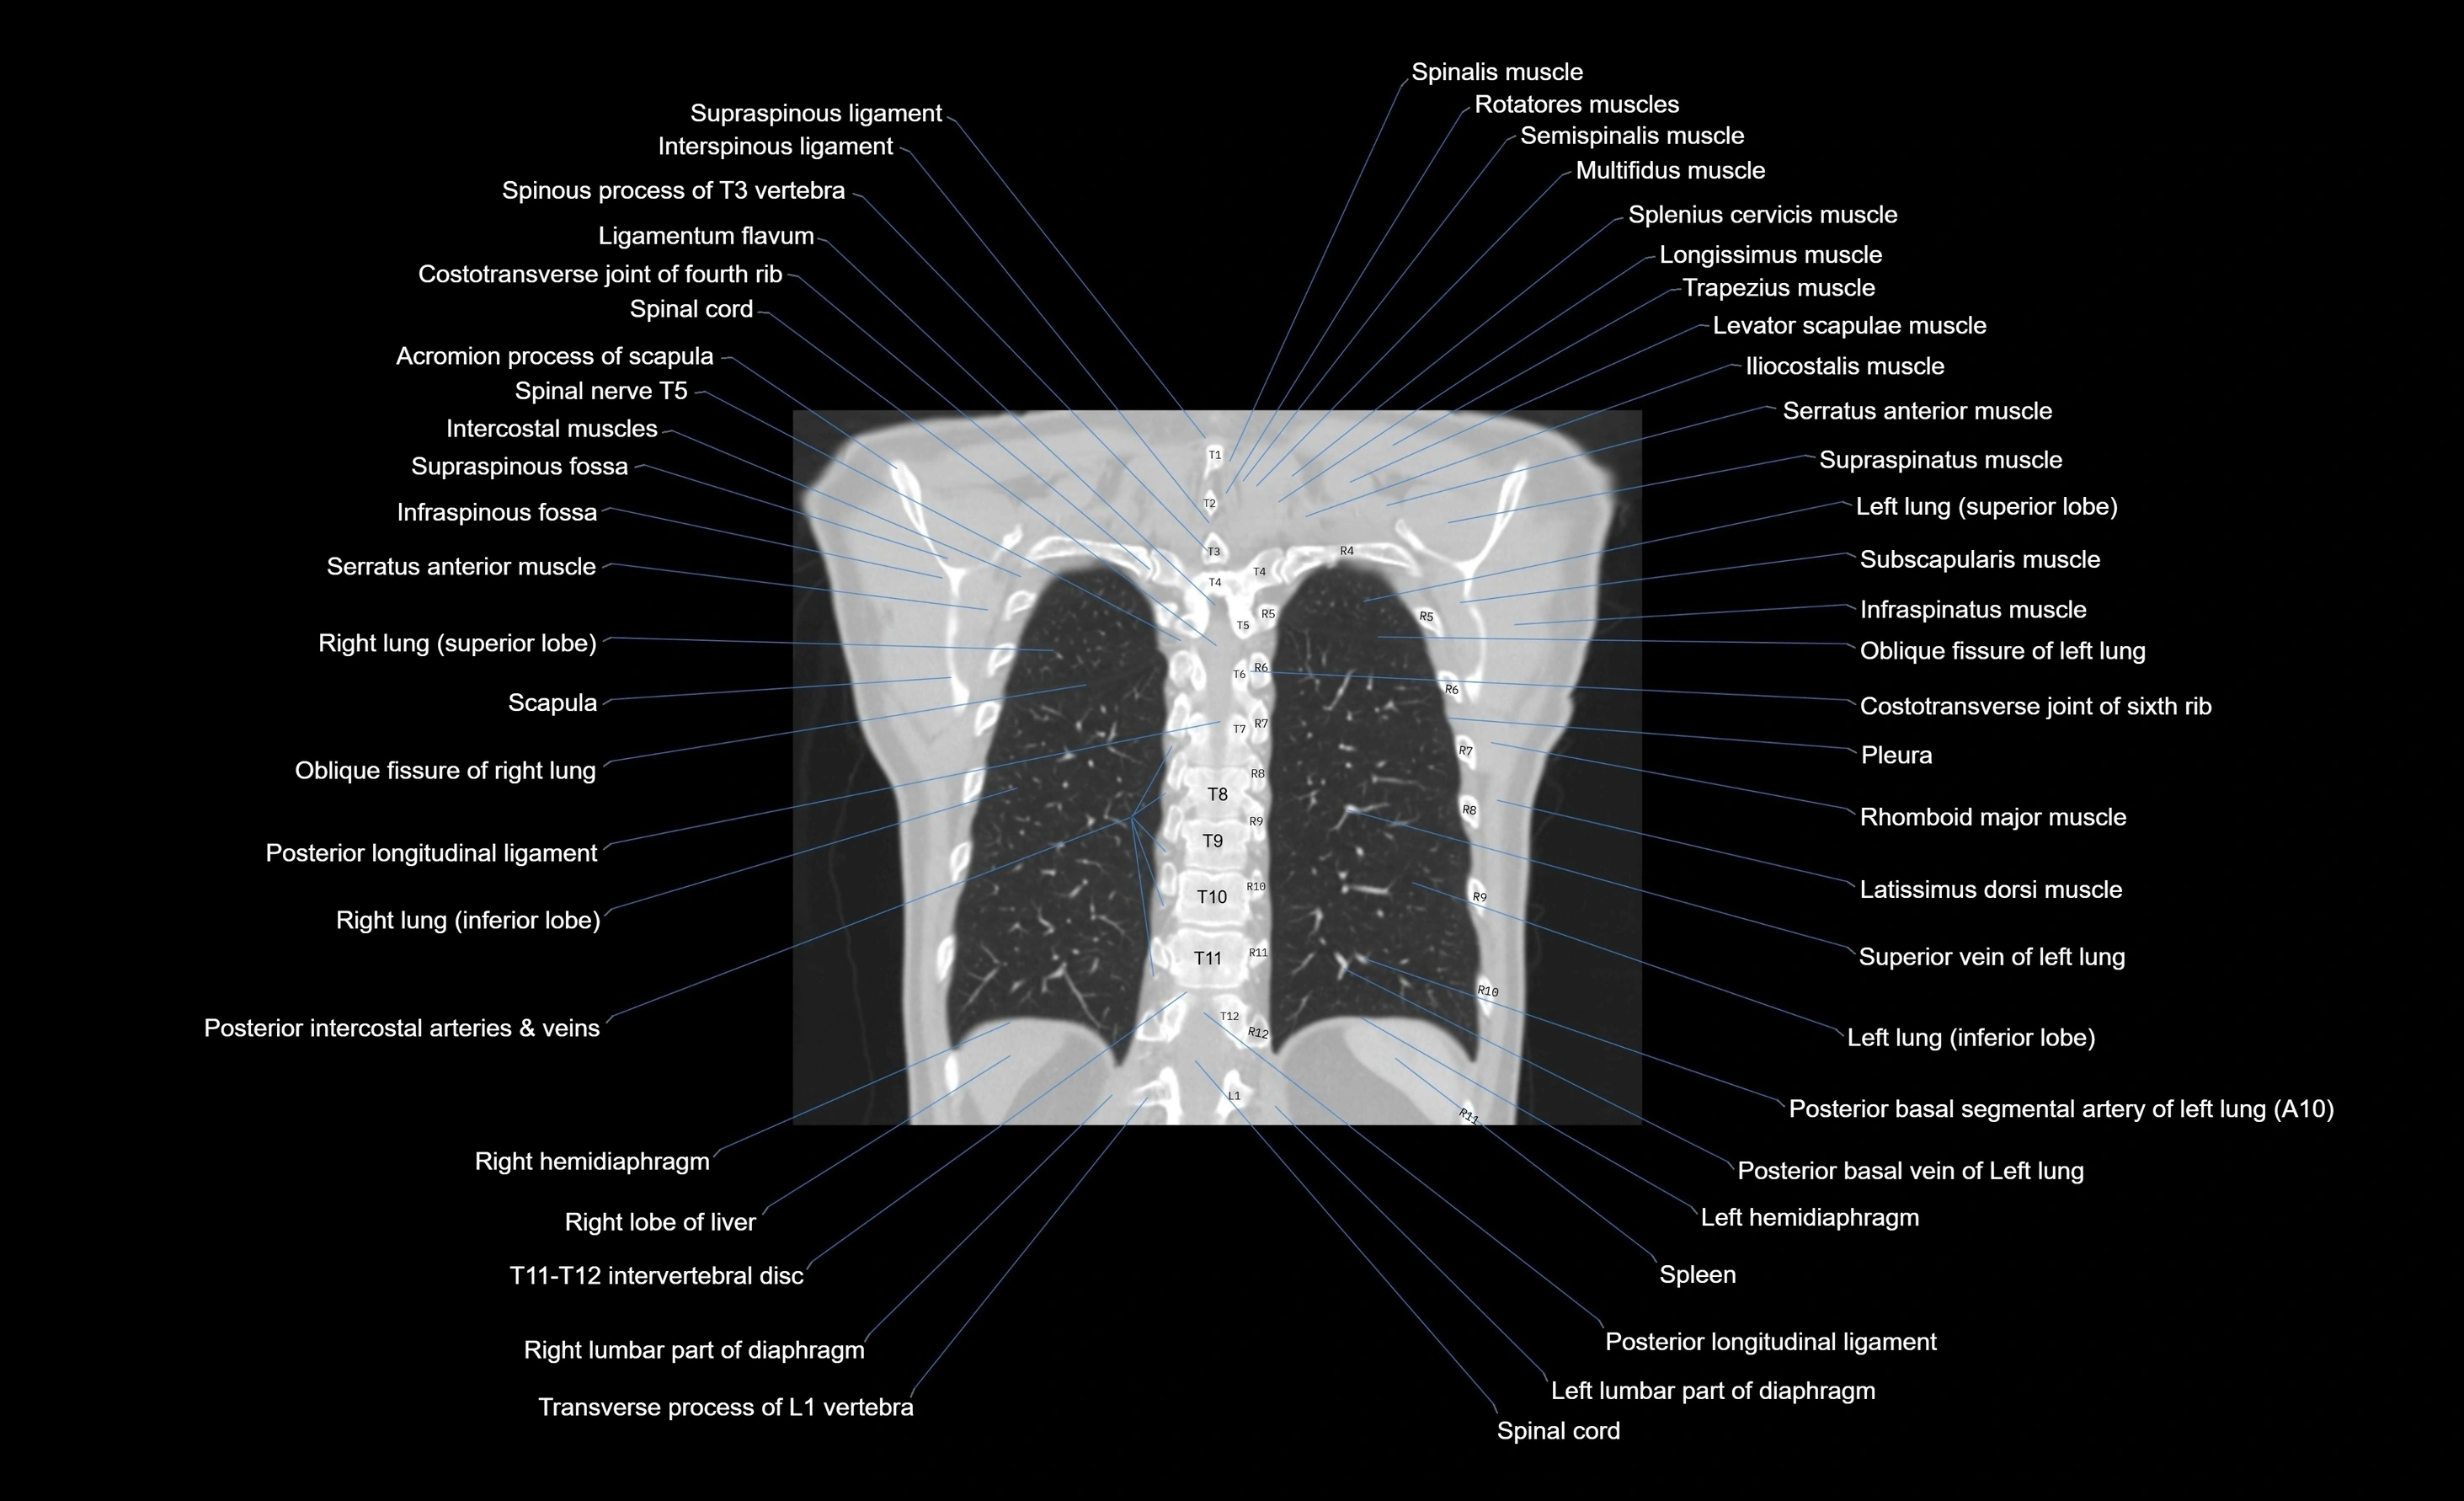

CT images